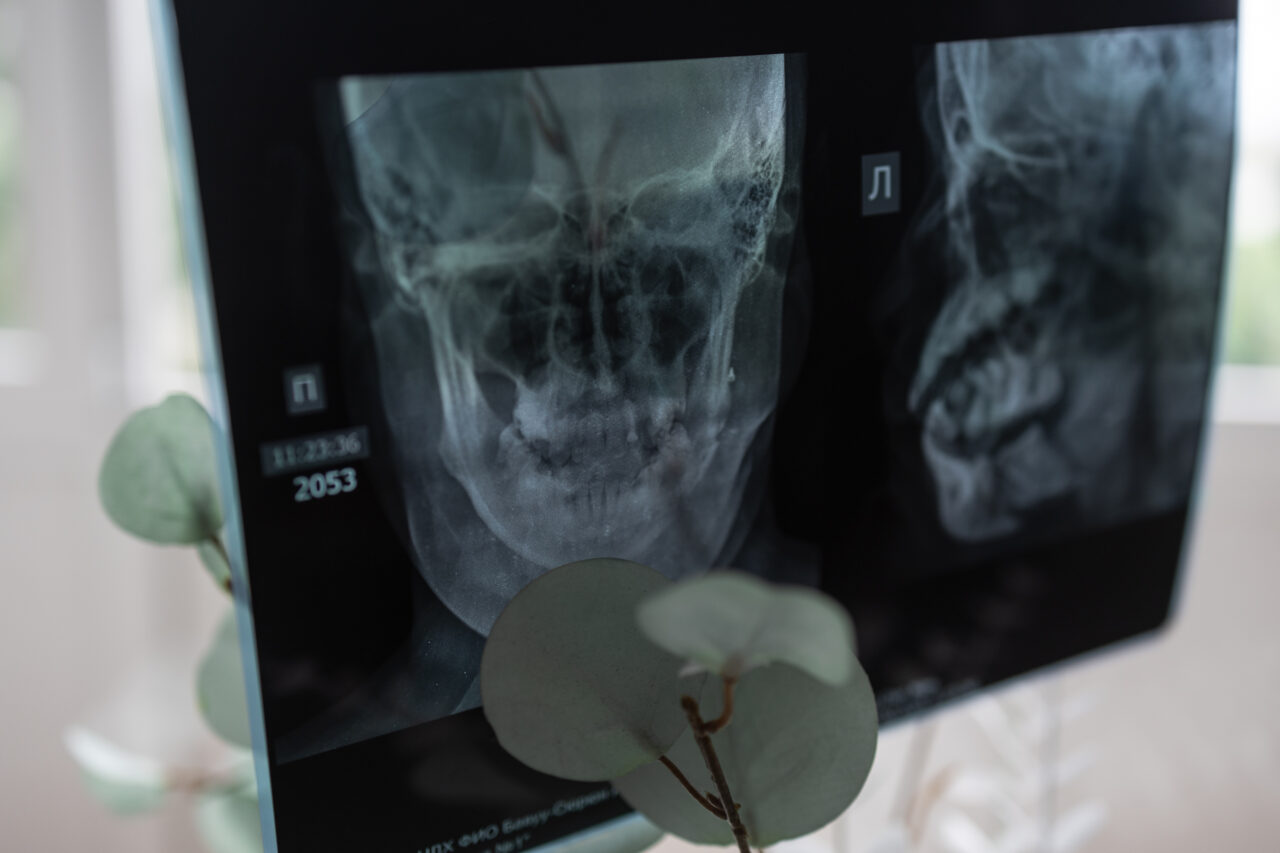

Борец и брат Аяны Айдын Монгуш в первые же часы пришел в больницу к сестре. Аяне сделали исследование на рентгене, она ждала врача в смотровом кабинете и была изумлена, когда брат появился. Он попросил сказать врачам и следователям, что в нее стреляли «приехавшие парни, хулиганы», а не депутат Саян. Аяна отказалась. Когда шок прошел, у Аяны упало давление, она потеряла сознание, сутки провела в реанимации. Следующую попытку убедить Аяну сделал сам депутат.

Из больницы Аяна вышла через 18 дней. Пуля повредила ее челюсть, обломки сместились, остатки двух зубов врачам пришлось удалить. Кроме того, были пробиты железа и артерия. Аяна оглохла на левое ухо. Дома у нее 2,5 месяца гноилась челюсть, ткани отторгали титановую пластину, которую вживили медики. Врачи сказали, что надо ждать, когда рана перестанет гноиться, и потом восстанавливать лицо.

Аяне уже сделали шесть операций. Речь пока не идет об эстетической медицине. Сначала нужно восстановить череп, вставить разрушенные зубы, исправить асимметрию, наладить слух. Потом уже приступать к пластическим операциям. Врачи пока не говорят, сколько это будет стоить. Ориентировочно — около 10 миллионов рублей.